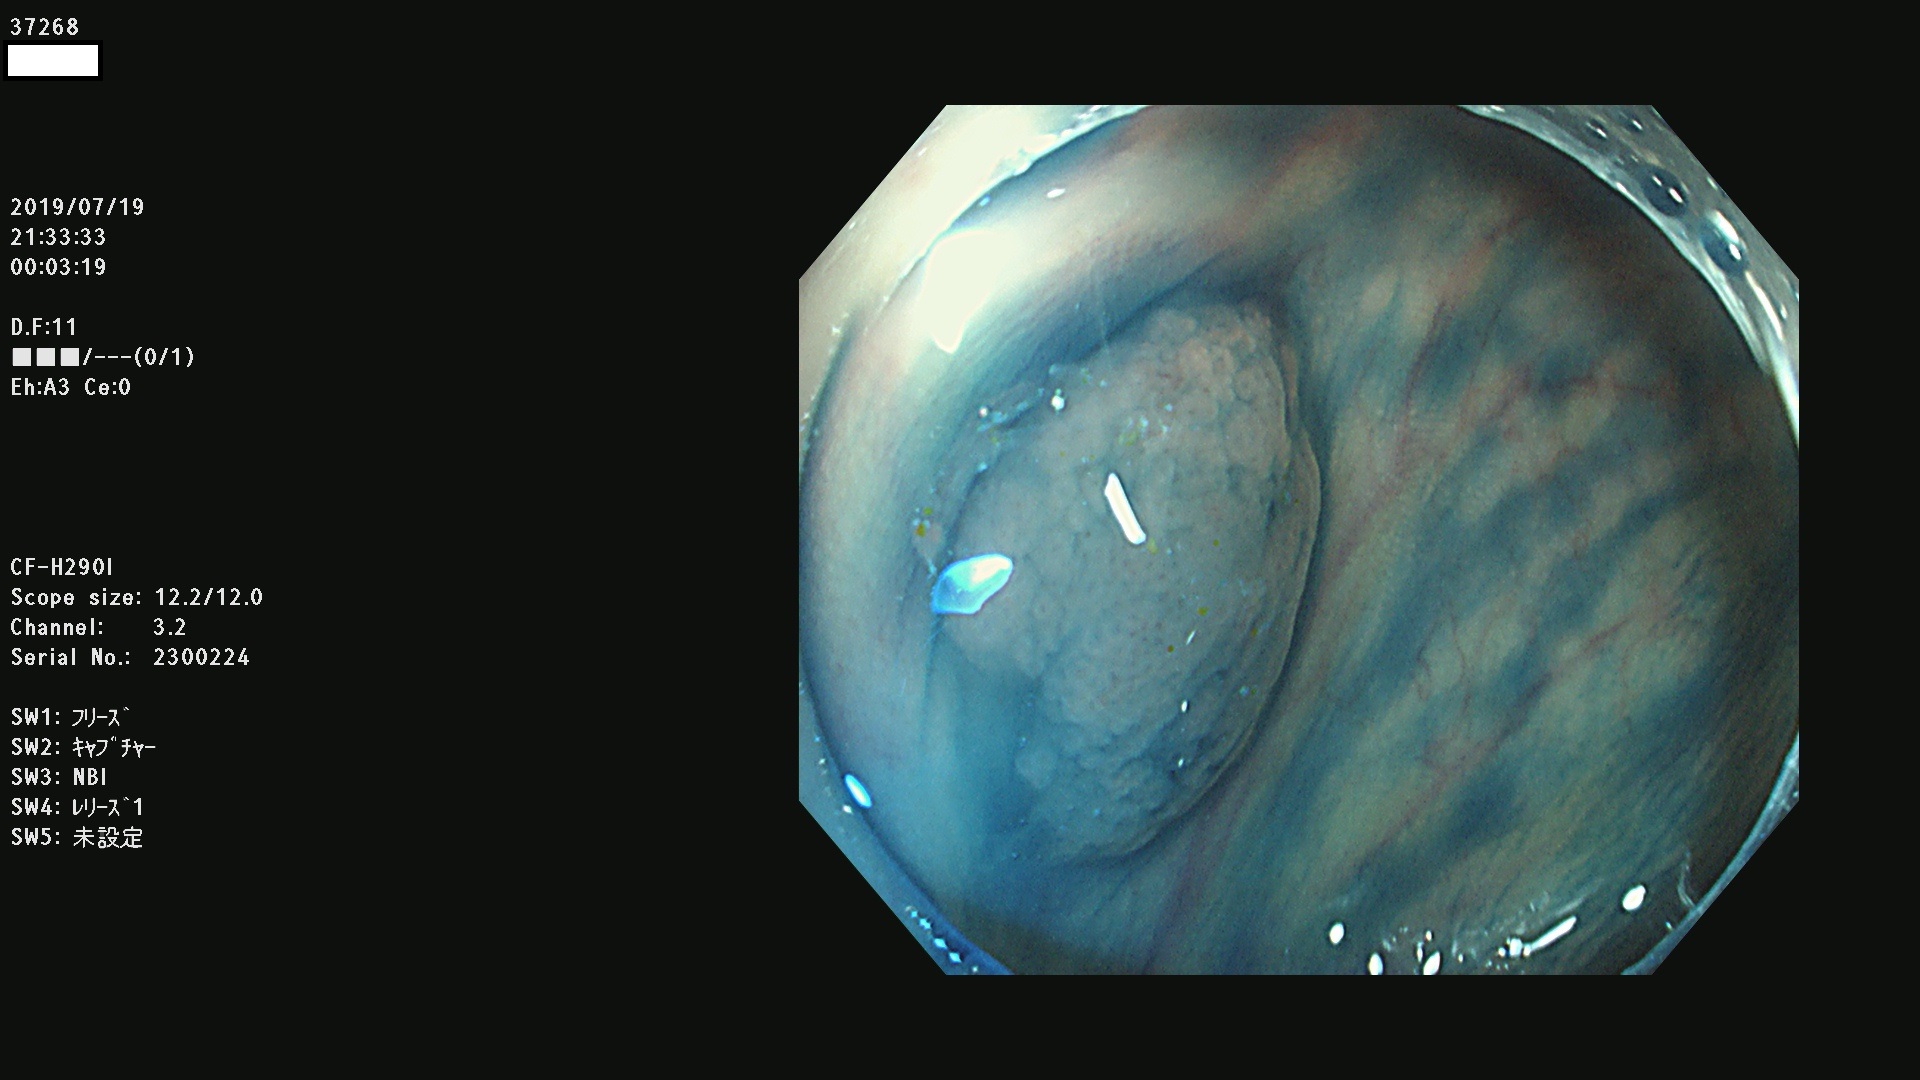

37200 37203 37204 37207 37208 37209 37210 37211 37212 37213 37214 37215 37216 37217 37220 37221 37222 37224 37225 37228 37229 37230 37232 37233 37234 37235 37236 37238 37241 37242 37243 37244 37245(SSAPのみ) 37247 37249 37250 37251 37252(SSAPのみ) 37254 37256 37257 37258 37259 37260(SSAPのみ) 37261(SSAPのみ) 37262 37263 37264 37265 37266 37267 37268(SSAPのみ) 37269 37271 37273 37274 37276 37277 37278 37279 37280 37281 37282 37284(SSAPのみ) 37285 37286 37288 37289 37290 37292 37293 37295 37296 37297(SSAPのみ)

発見困難で危険性の高い平坦型病変(上記100名より抽出)